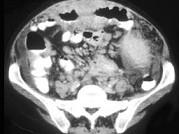

问题 男,46岁,患者低热、乏力,时有腹痛,请结合图像,选择最可能诊断()

选项 A.横结肠癌 B.横结肠淋巴瘤 C.横结肠转移瘤 D.假膜性肠炎 E.溃疡性结肠炎

答案 B